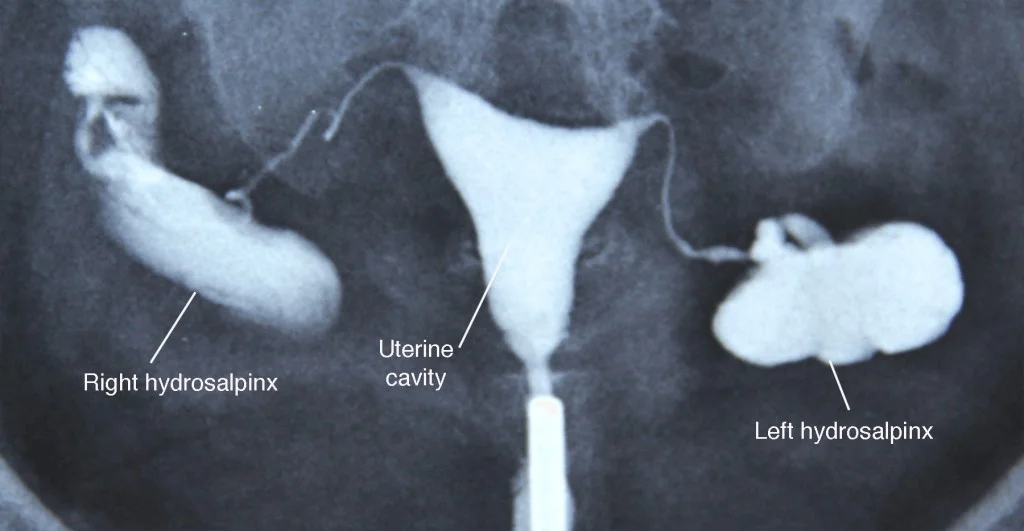

Hysterosalpingography (HSG)

Application of contrast agent into the uterine cavity:

Indications :

- infertility to assess :

- uterine morphology

- tubal patency.

Technique

- performed during proliferative phase

- the menstrual cycle (days 6-12)

- β¦when the endometrium is at its thinnest

- patient in the lithotomy position

- Vaginal speculum is inserted with the cervix in view

- the cervix is cleaned with an aseptic solution

- catheterization of the cervix.

- Inject contrast.

The image contains three X-ray images with labels and annotations.

- The top-left image is labeled with the following text:

- Right hydrosalpinx

- Uterine cavity

- Left hydrosalpinx

Complications

- Common but self-limiting β abdominal cramping β spotting β venous extravasation

- Rare but serious β pelvic infection β contrast reaction